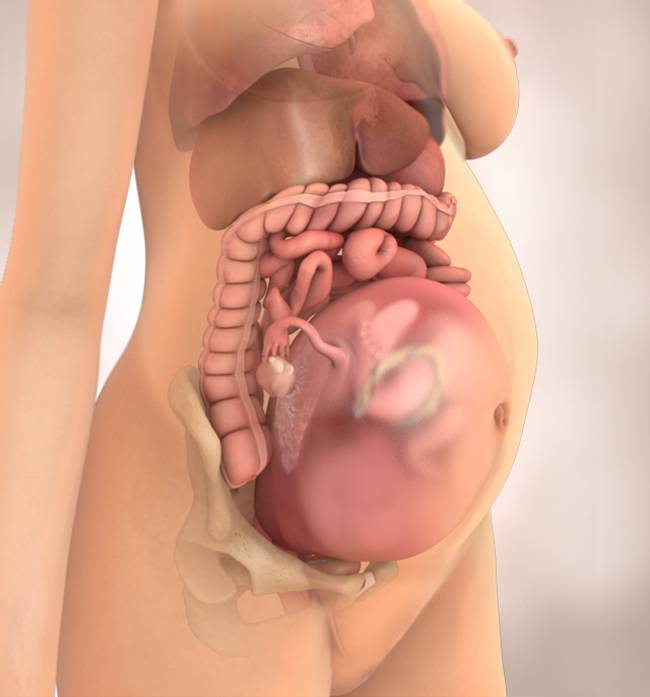

Фотография Плода В Животе

Фотография Плода В Животе 113 фотографий